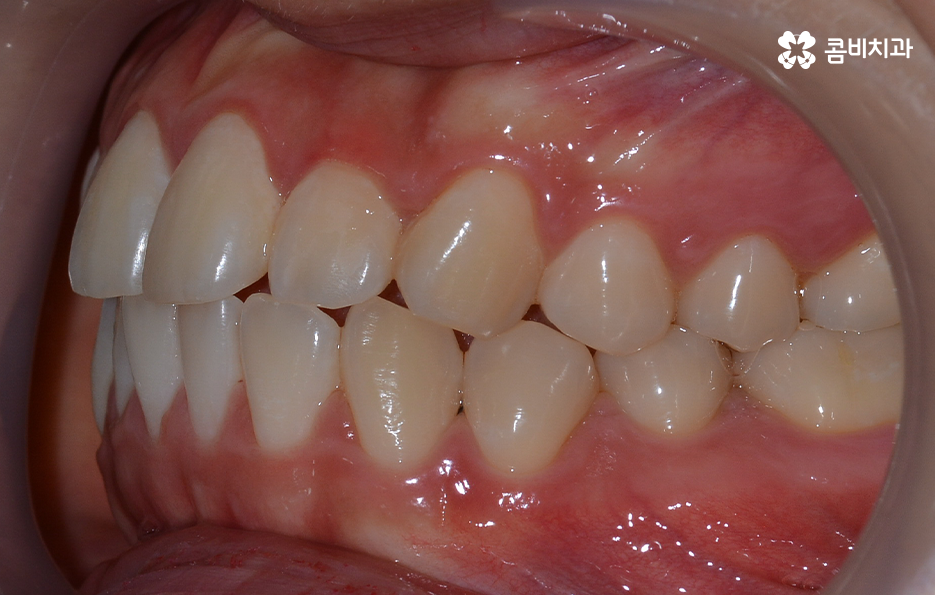

보통 치아교정을 통해 눈에 띄게 얼굴 변화를 느끼게 되는 경우는 쉽게 말해 발치를 통한 교정으로 볼 수 있어요. 그 이유는 치아를 발치하게 되면 발치한 만큼의 공간이 악궁에서 축소가 되기 때문에 그로 인해 얼굴라인이 갸름하게 변하게 되거나 돌출입발치교정 같이 돌출입의 개선이 되는 거예요

치아를 발치하고 이동하면서 얼굴 변화의 대표적 사례는 돌출입 개선이나 얼굴 라인의 변화뿐 아니라 얼굴 비대칭의 개선이나 팔자주름이 옅어지는 등의 변화를 꼽을 수 있어요

영구치를 발치하는 것에 대한 두려움이나 거부감을 갖고 있는 분들의 경우 발치보다는 비발치로 치아교정을 원하시는 분들도 많이 계실 거예요. 하지만 발치가 아닌 비발치로 교정을 진행할 경우 치아가 움직일 수 있는 양의 한계가 있기 때문에 얼굴 변화는 크지 않다고 볼 수 있어요